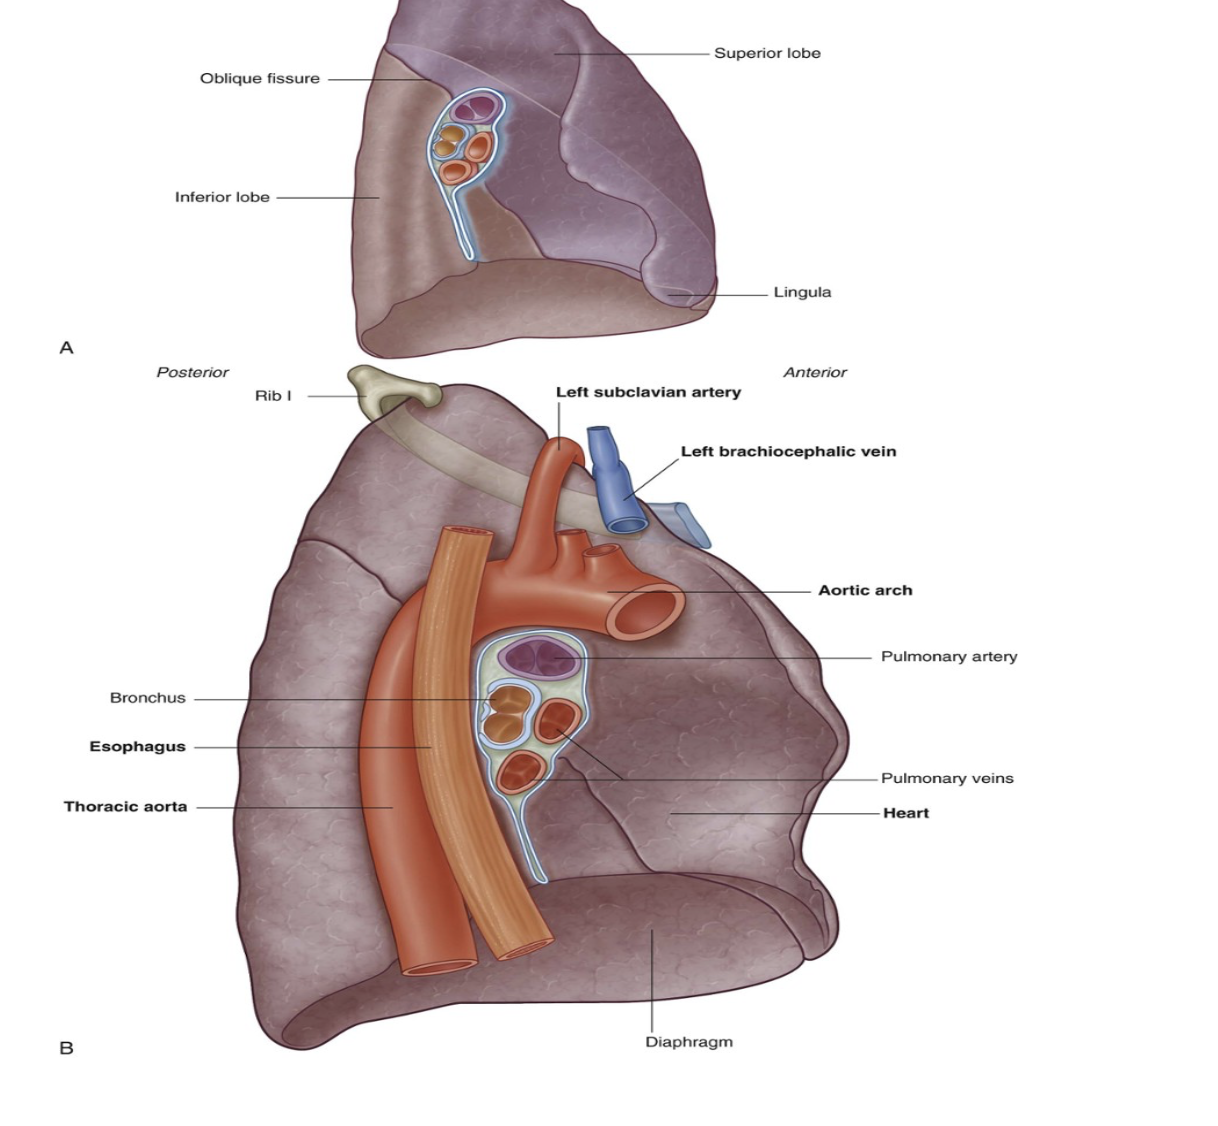

Left lung lobes & fissure

2 — superior & inferior, with fissure separating them

Superior lobe —

In contact with upper part of anterolateral wall & apex of this lobe projects into the root of the neck contact

Costal surface of inferior lobe — in contact with posterior & inferior walls

Oblique fissure —

Separates superior & inferior lobe — slightly more oblique than that on right lung

Left lung is slightly smaller than right lung due to heart on left side (thus left lung has corresponding cardiac notch & additionally the associated lingula of the left lung which projects over the heart bulge

Important structures in the mediastinum & root of neck that are adjacent to medial surface of left lung

Heart

Aortic arch,

Thoracic aorta

Esophagus

Note about subclavian vessels & left lung

The left subclavian artery and vein arch over and are related to the superior lobe of the left lung as they pass over the dome of the cervical pleura and into the axilla